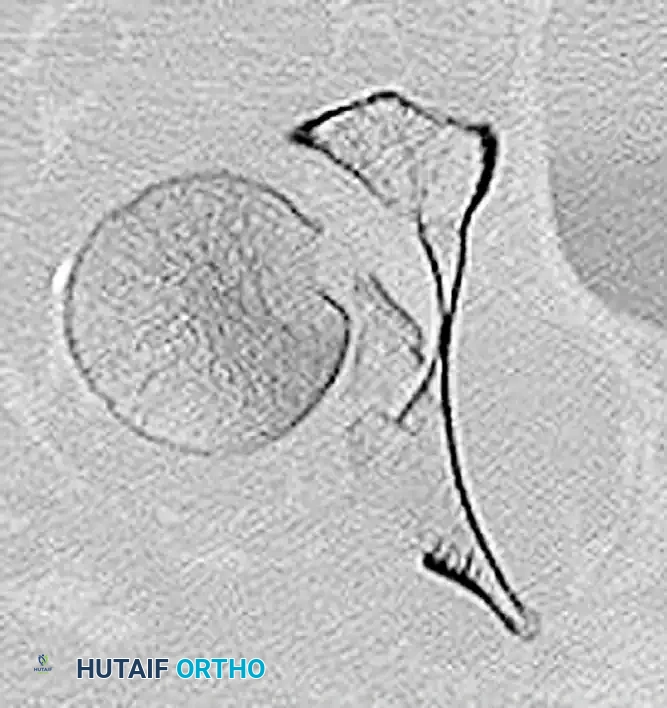

Figure 55-63A: Preoperative radiograph of a femoral shaft fracture. The subtle nondisplaced femoral neck fracture was initially missed.

Figure 55-63B: Intraoperative fluoroscopic view after placement of an antegrade intramedullary nail. Note the appearance of the proximal femur.

Figure 55-63C: Intraoperative fluoroscopic view after range of motion of the hip under live fluoroscopy reveals the previously occult femoral neck fracture.